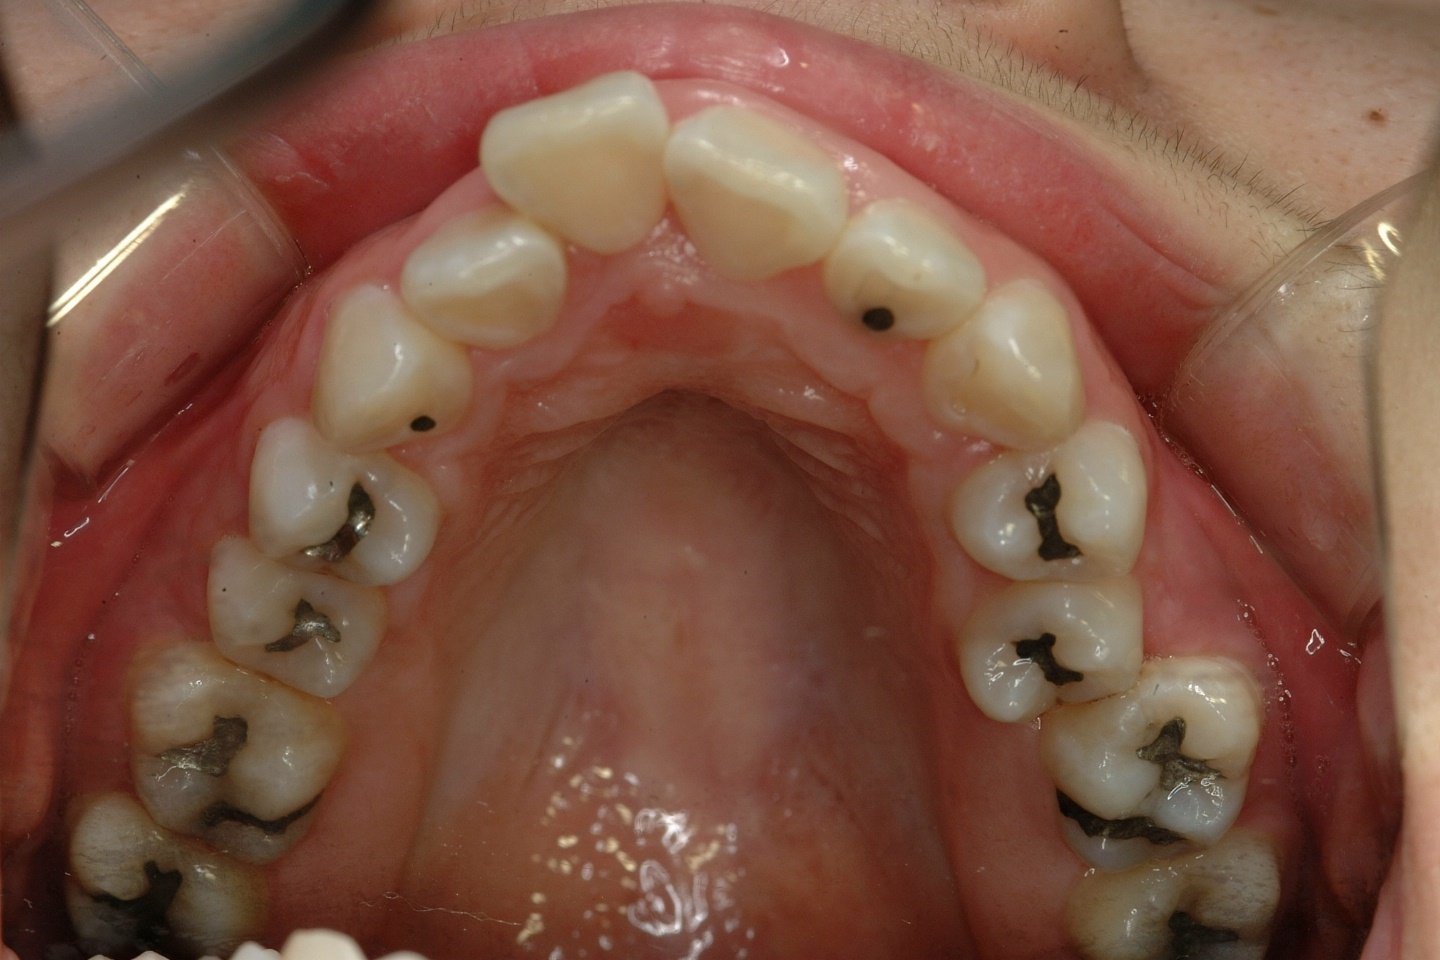

치료 전 사진입니다.